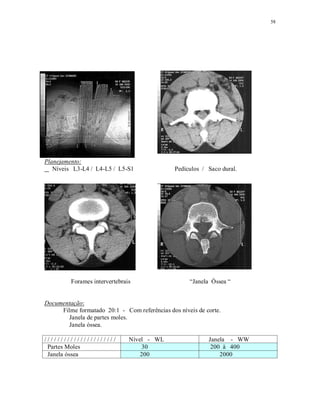

Planejamento:

Níveis L3-L4 / L4-L5 / L5-S1 Pedículos / Saco dural.

Forames intervertebrais “Janela Óssea “

Documentação:

Filme formatado 20:1 - Com referências dos níveis de corte.

Janela de partes moles.

Janela óssea.

/ / / / / / / / / / / / / / / / / / / / / / Nível - WL Janela - WW

Partes Moles 30 200 à 400

Janela óssea 200 2000